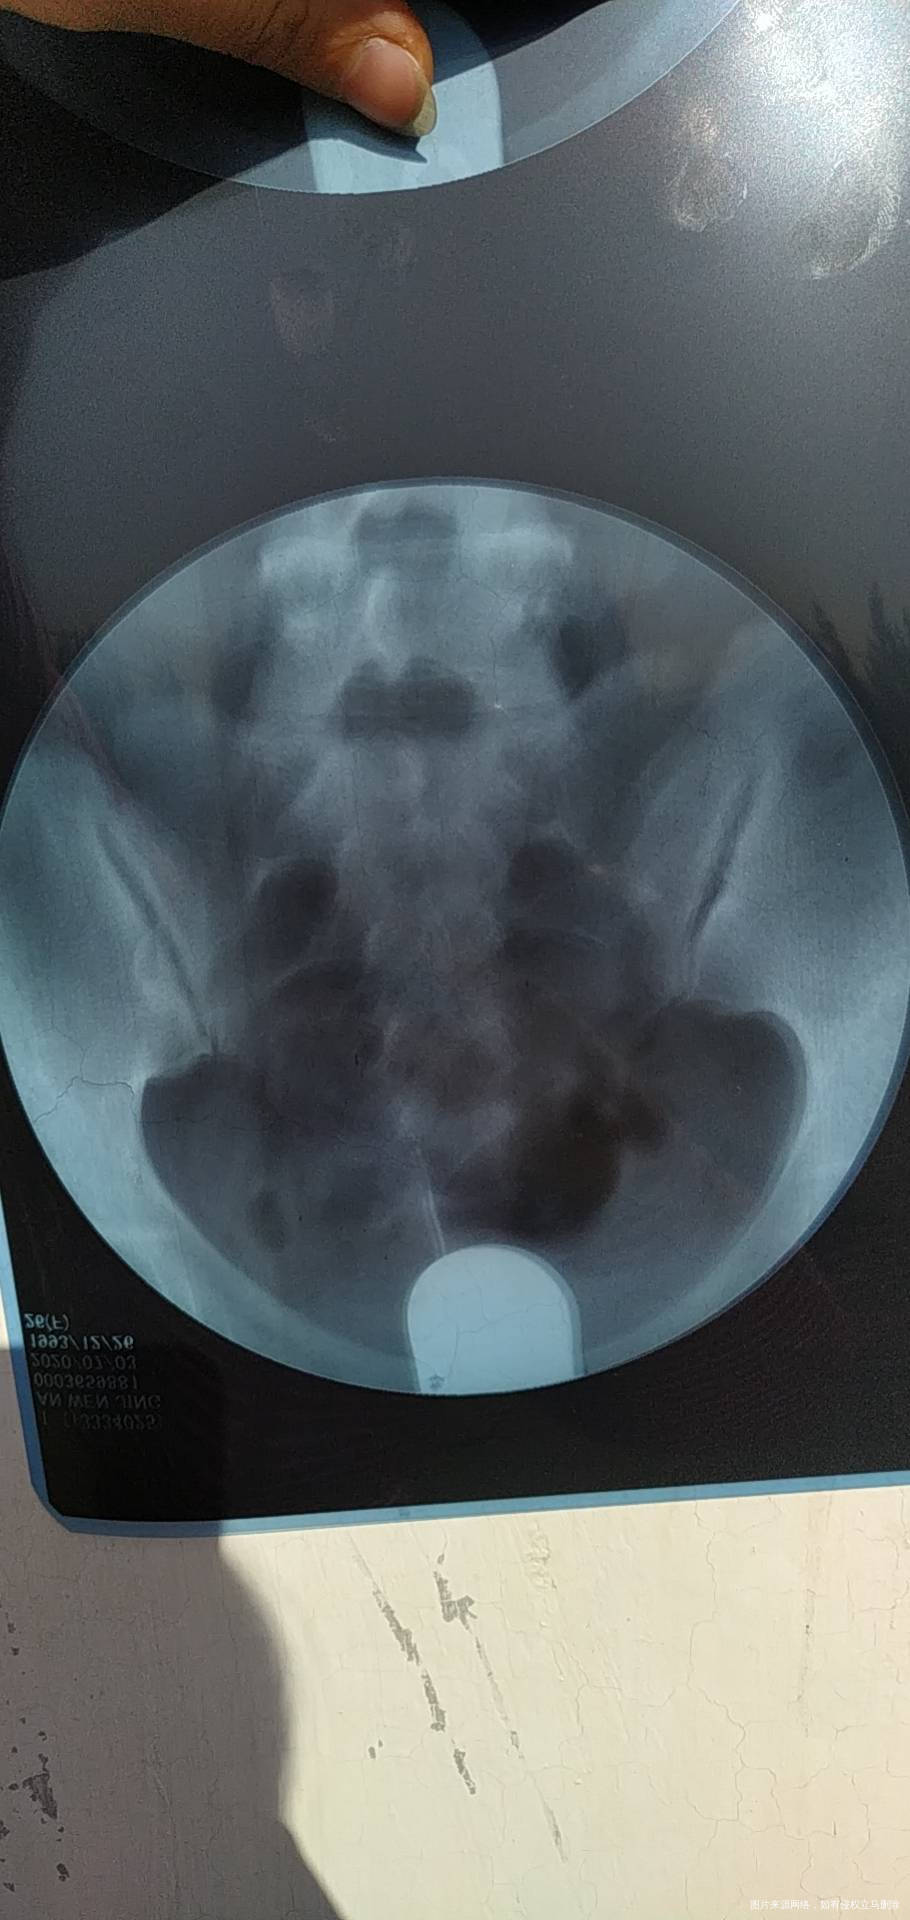

今年七月份做的造影。显示输卵管通而不畅,伴随多囊卵巢,喝中药调理了5个月,促排了两次,均失败。医生建议我直接试管,我想问一下各位专家,我还有自然受孕的机会吗?

亲,输卵管通而不畅不是代表完全不通,还是可以自己试试,多囊卵巢现在有的人太多了。你促排失败是什么原因要找找,胰岛素有抵抗吗,还是血糖油膏?这个内分没问题一般是没事,先可以深继续促排治疗